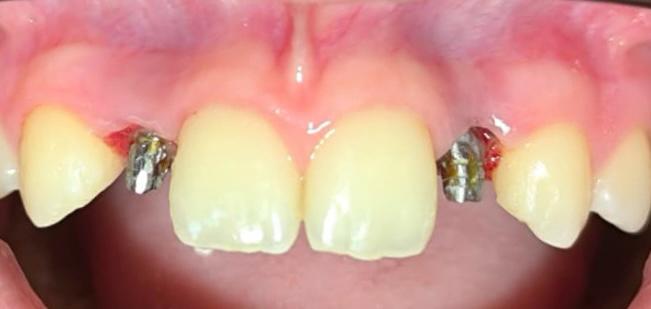

Lo que realmente nos diferencia es la carga inmediata. No queremos que salgas de nuestra clínica con un hueco en tu sonrisa. En el mismo momento de la cirugía, preparamos coronas provisionales que no solo devuelven la estética, sino que ayudan a que tu encía se cure con la forma perfecta.

El éxito de este caso, que terminó con una paciente feliz y una sonrisa renovada, no es fruto del azar. Es el resultado de combinar la dilatada experiencia del Dr. Dario Castro con la tecnología de Microdent y una visión centrada en la comodidad del paciente.